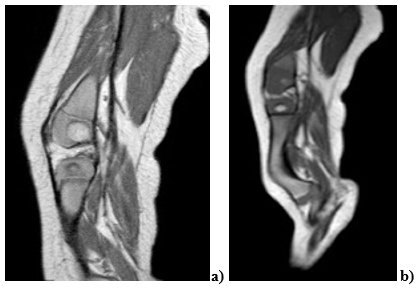

El primer caso documentado es de un bebé de 6 meses de edad, a quien en estudios prenatales se le había detectado ausencia del peroné derecho y oligodactilia por agenesia del quinto metacarpiano (figura 1). En el examen físico presentaba acortamiento del miembro inferior izquierdo con arqueamiento anterior de la pierna, pie equino valgo, oligodactilia e inestabilidad de la rodilla por hipoplasia del ligamento cruzado anterior (figura 2).

a) Hipoplasia del ligamento cruzado anterior de la rodilla derecha. b) Hay acortamiento y arqueamiento anterior de la tibia derecha con marcada atrofia muscular